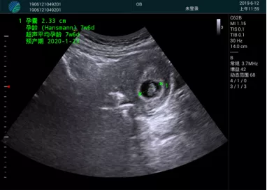

病例一:

清晰顯示孕囊,通過(guò)軟件包計算孕齡7w+6d

M20實(shí)時(shí)引導,術(shù)中清晰顯示孕囊被破壞和抽吸針的過(guò)程,清晰顯示吸引針

抽吸結束后縱切子宮,孕囊已被完全抽吸,未見(jiàn)明顯殘留

橫切子宮,發(fā)現右側宮腔靠近宮角處有少許脫模樣殘留

M20引導下,抽吸針找到右側宮角處再次清掃

二次抽吸后再次進(jìn)行超聲檢查,宮腔未見(jiàn)殘留,宮腔線(xiàn)清晰顯示

超聲引導下可視化人流是技術(shù)安全性的保障,一般對人流術(shù)設備預算不高,M20具備婦產(chǎn)科軟件包,且穿透力圖像質(zhì)量好,既滿(mǎn)足人流引導需要,也可用于床旁超聲的需求。